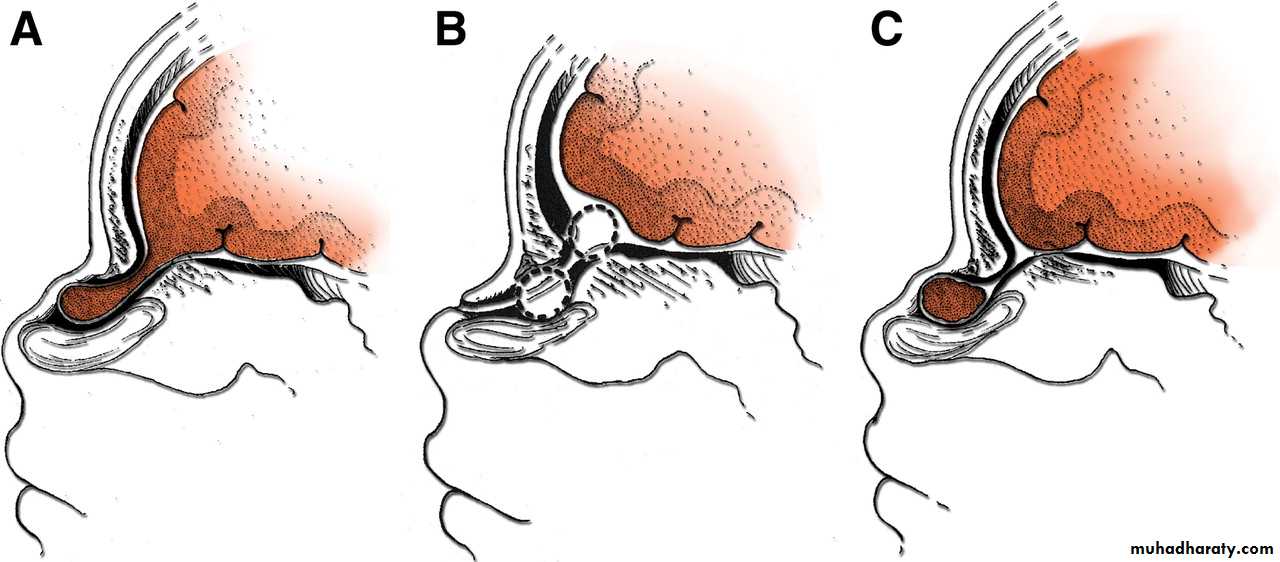

Types of spina bifida:

Spina bifida Occulta

Spina bifida Cystica

Spina bifida Aperta

• Spina bifida Occulta:

• The posterior vertebral arch has a defect within it, but there is no herniation of the neural tube.

• 2. Spina bifida Cystica:

• In this situation there is skin covering the defect making a cyst like.

• If this cyst contains CSF only it is called MENINGOCELE.

• If there is neural tissue within the sac, it is called MYELOMENINGOCELE.

SPINA BIFIDA

• 3. Spina bifida Aperta:

• The neural tube is open with no skin coverage, through a defect in the posterior vertebral arch.